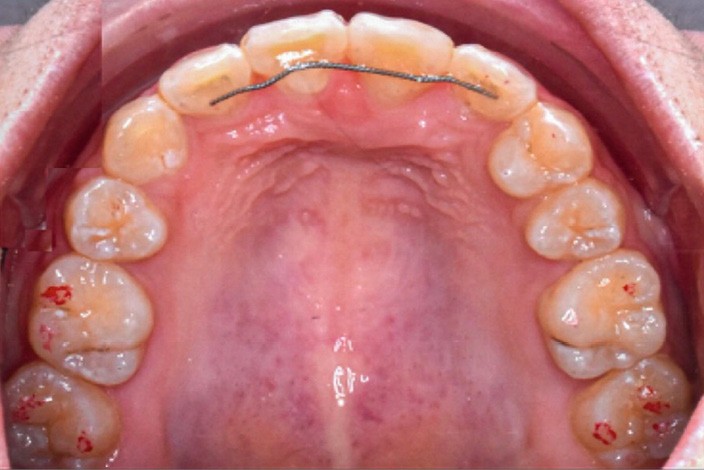

Une patiente âgée de 12 ans se présente en consultation, motivée par la position de son incisive centrale maxillaire, décrite comme « en avant », marquée par une dyschromie et une mobilité de grade 2 selon Muhlemann. L’examen clinique montre l’absence de 23 sur l’arcade, une dysharmonie dents-arcade marquée, un surplomb accentué, et une déviation des milieux inter-incisifs, conséquence du comblement spontané de l’espace de 23. L’ensemble s’inscrit dans un contexte de Classe I d’Angle molaire. L’orthopantomogramme révèle l’inclusion de 23, associée à une résorption radiculaire étendue aux deux tiers de 21. La 22 ne présente aucune altération visible.

La patiente, de profil normodivergent, présente une Classe I squelettique sans troubles fonctionnels (fig. 1-8).